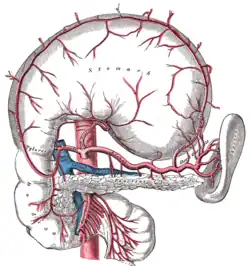

![]() The abdominal aorta and its branches. | |

- inferior phrenic a.

- celiac a.

- left gastric a.

- splenic a.

- short gastric arteries (6)

- splenic arteries (6)

- left gastroepiploic a.

- pancreatic arteries

- common hepatic a.

- right gastric a.

- gastroduodenal a.

- right gastroepiploic a.

- superior pancreaticoduodenal a.

- right hepatic a.

- cystic a.

- left hepatic a.

- superior mesenteric a.

- inferior pancreaticoduodenal a.

- jejunal and ileal arteries

- middle colic a.

- right colic a.

- ileocolic a

- anterior cecal a.

- posterior cecal a. – appendicular a.

- ileal a.

- colic a.

- middle suprarenal a.

- renal a.

- testicular or ovarian a.

- four lumbar arteries

- inferior mesenteric a.

- left colic a.

- sigmoid arteries (2 or 3)

- superior rectal a.

- median sacral a.

- common iliac a.

- external iliac a.

- internal iliac a.

The celiac artery and its branches; the stomach has been raised and the peritoneum removed.